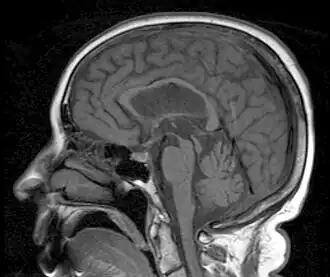

MRI demonstrating the hummingbird sign of supranuclear palsy due to atrophy of the midbrain

Magnetic resonance imaging (MRI) is often used to diagnose PSP. MRI may show atrophy in the midbrain with preservation of the pons giving a "hummingbird" sign.[3][40]

The "humming-bird" imaging feature, indicative of midbrain degeneration, supports early diagnosis of both PSP-RS and PSP-P.[4][49] One commonly used quantitative measure is the midbrain-to-pons area ratio, which is calculated by measuring the cross-sectional areas of the midbrain and pons on midsagittal MRI images.[14]In healthy individuals, the midbrain and pons are proportionally sized, but in PSP-RS, the midbrain undergoes significant atrophy while the pons remains relatively spared.[14][13][49][50] As a result, the ratio is markedly reduced in PSP-RS, distinguishing it from other neurodegenerative conditions such as Parkinson’s disease, multiple system atrophy (MSA), and even PSP-P, which typically exhibit less pronounced midbrain atrophy.[14][13][49][50] To improve diagnostic specificity, the magnetic resonance parkinsonism index (MRPI) incorporates the midbrain-to-pons area ratio along with measurements of the widths of the middle and superior cerebellar peduncles.[14] The MRPI has been shown to enhance discrimination between PSP-RS and other forms of atypical parkinsonism.[14] Additional MRI findings associated with PSP-RS may include third ventricle enlargement, thinning of the superior cerebellar peduncles, and frontal lobe atrophy, all of which are consistent with the underlying tau pathology seen in the disease.[14] Brain atrophy in PSP-RS is generally symmetrical, which may correspond to the bilateral presentation of motor and cognitive symptoms.[17]